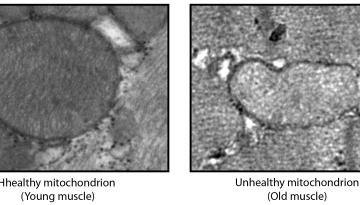

Publicat a Aging Cell

2022: Enguany, s'han realitzat avenços notables en la investigació sobre el càncer i la metàstasi i els transtorns relacionats amb el metabolisme i l’envelliment. També s’ha progressat en la comprensió fonamental dels mecanismes subjacents a la salut i a la malaltia. La nostra recerca ha tingut un gran impacte, tant en la comunitat científica com en la societat en general.